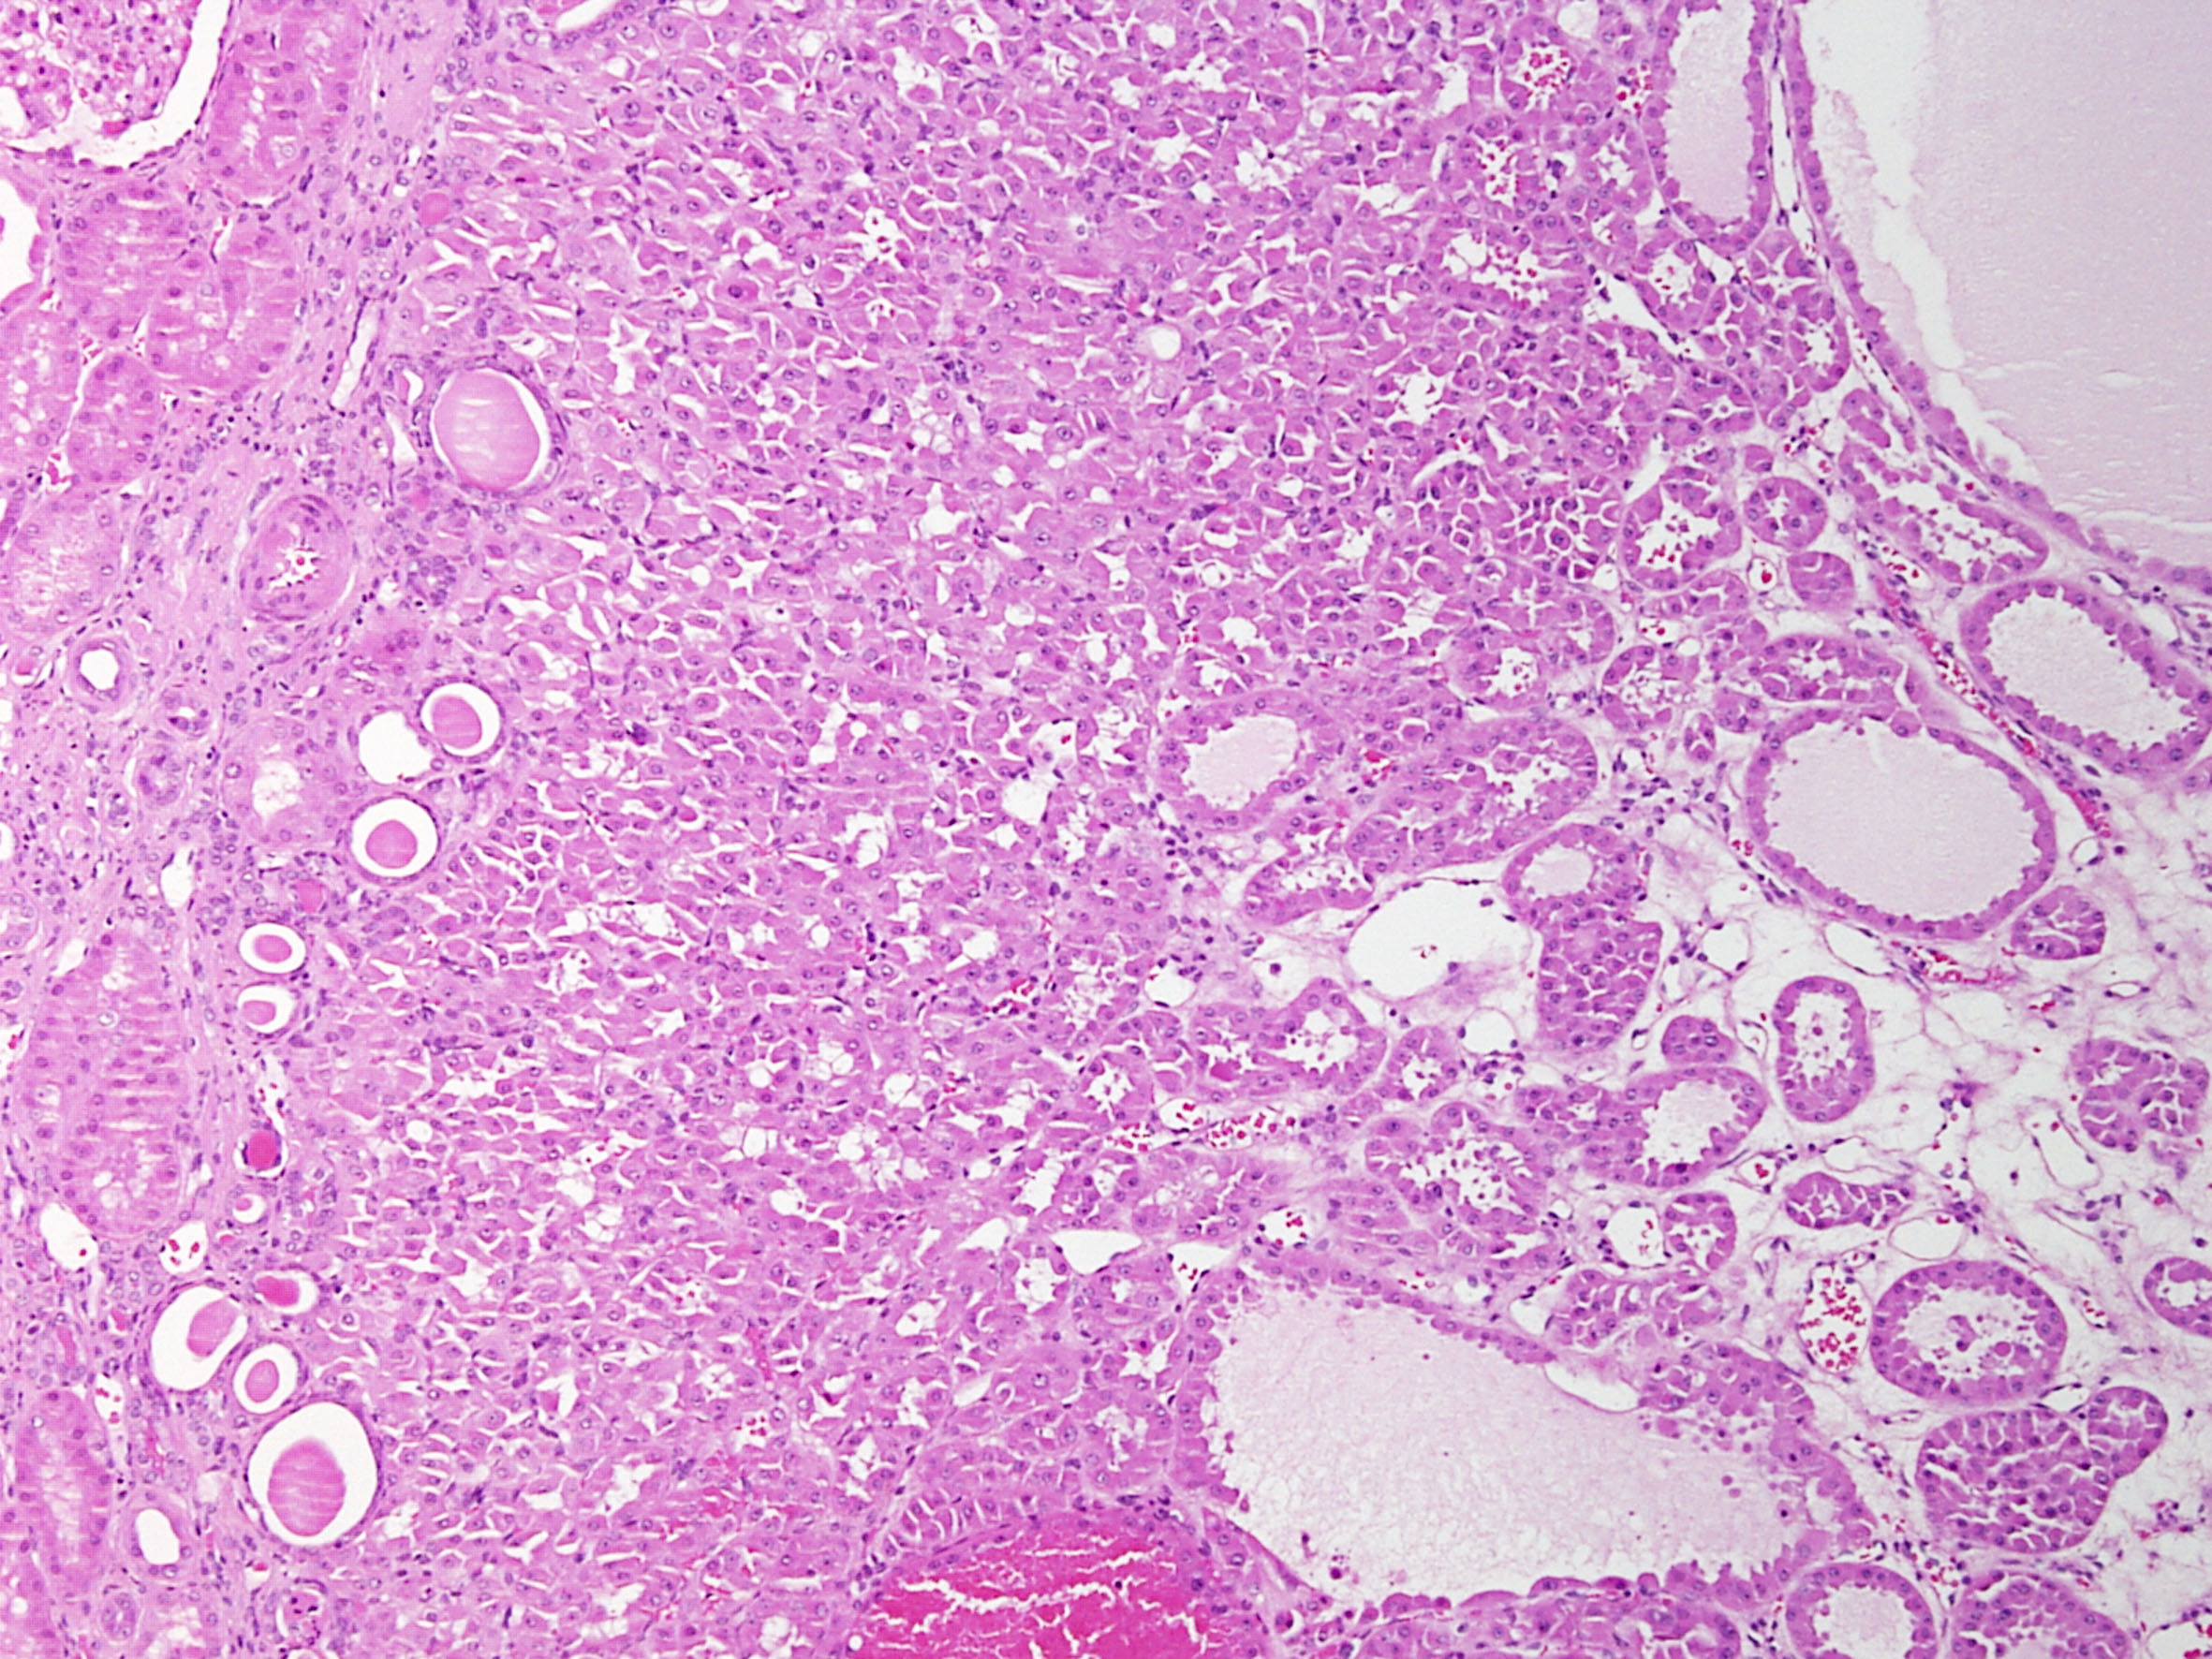

Consensus grade: oncocytoma

Case description (by case creator):

Oncocytoma